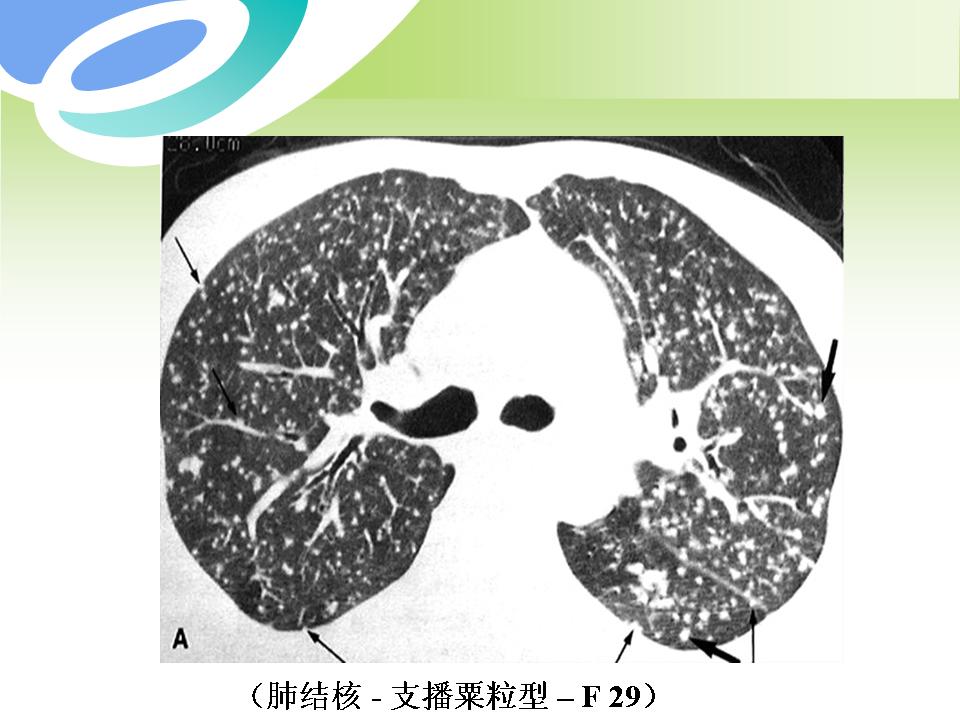

肺部病变的CT基本征象